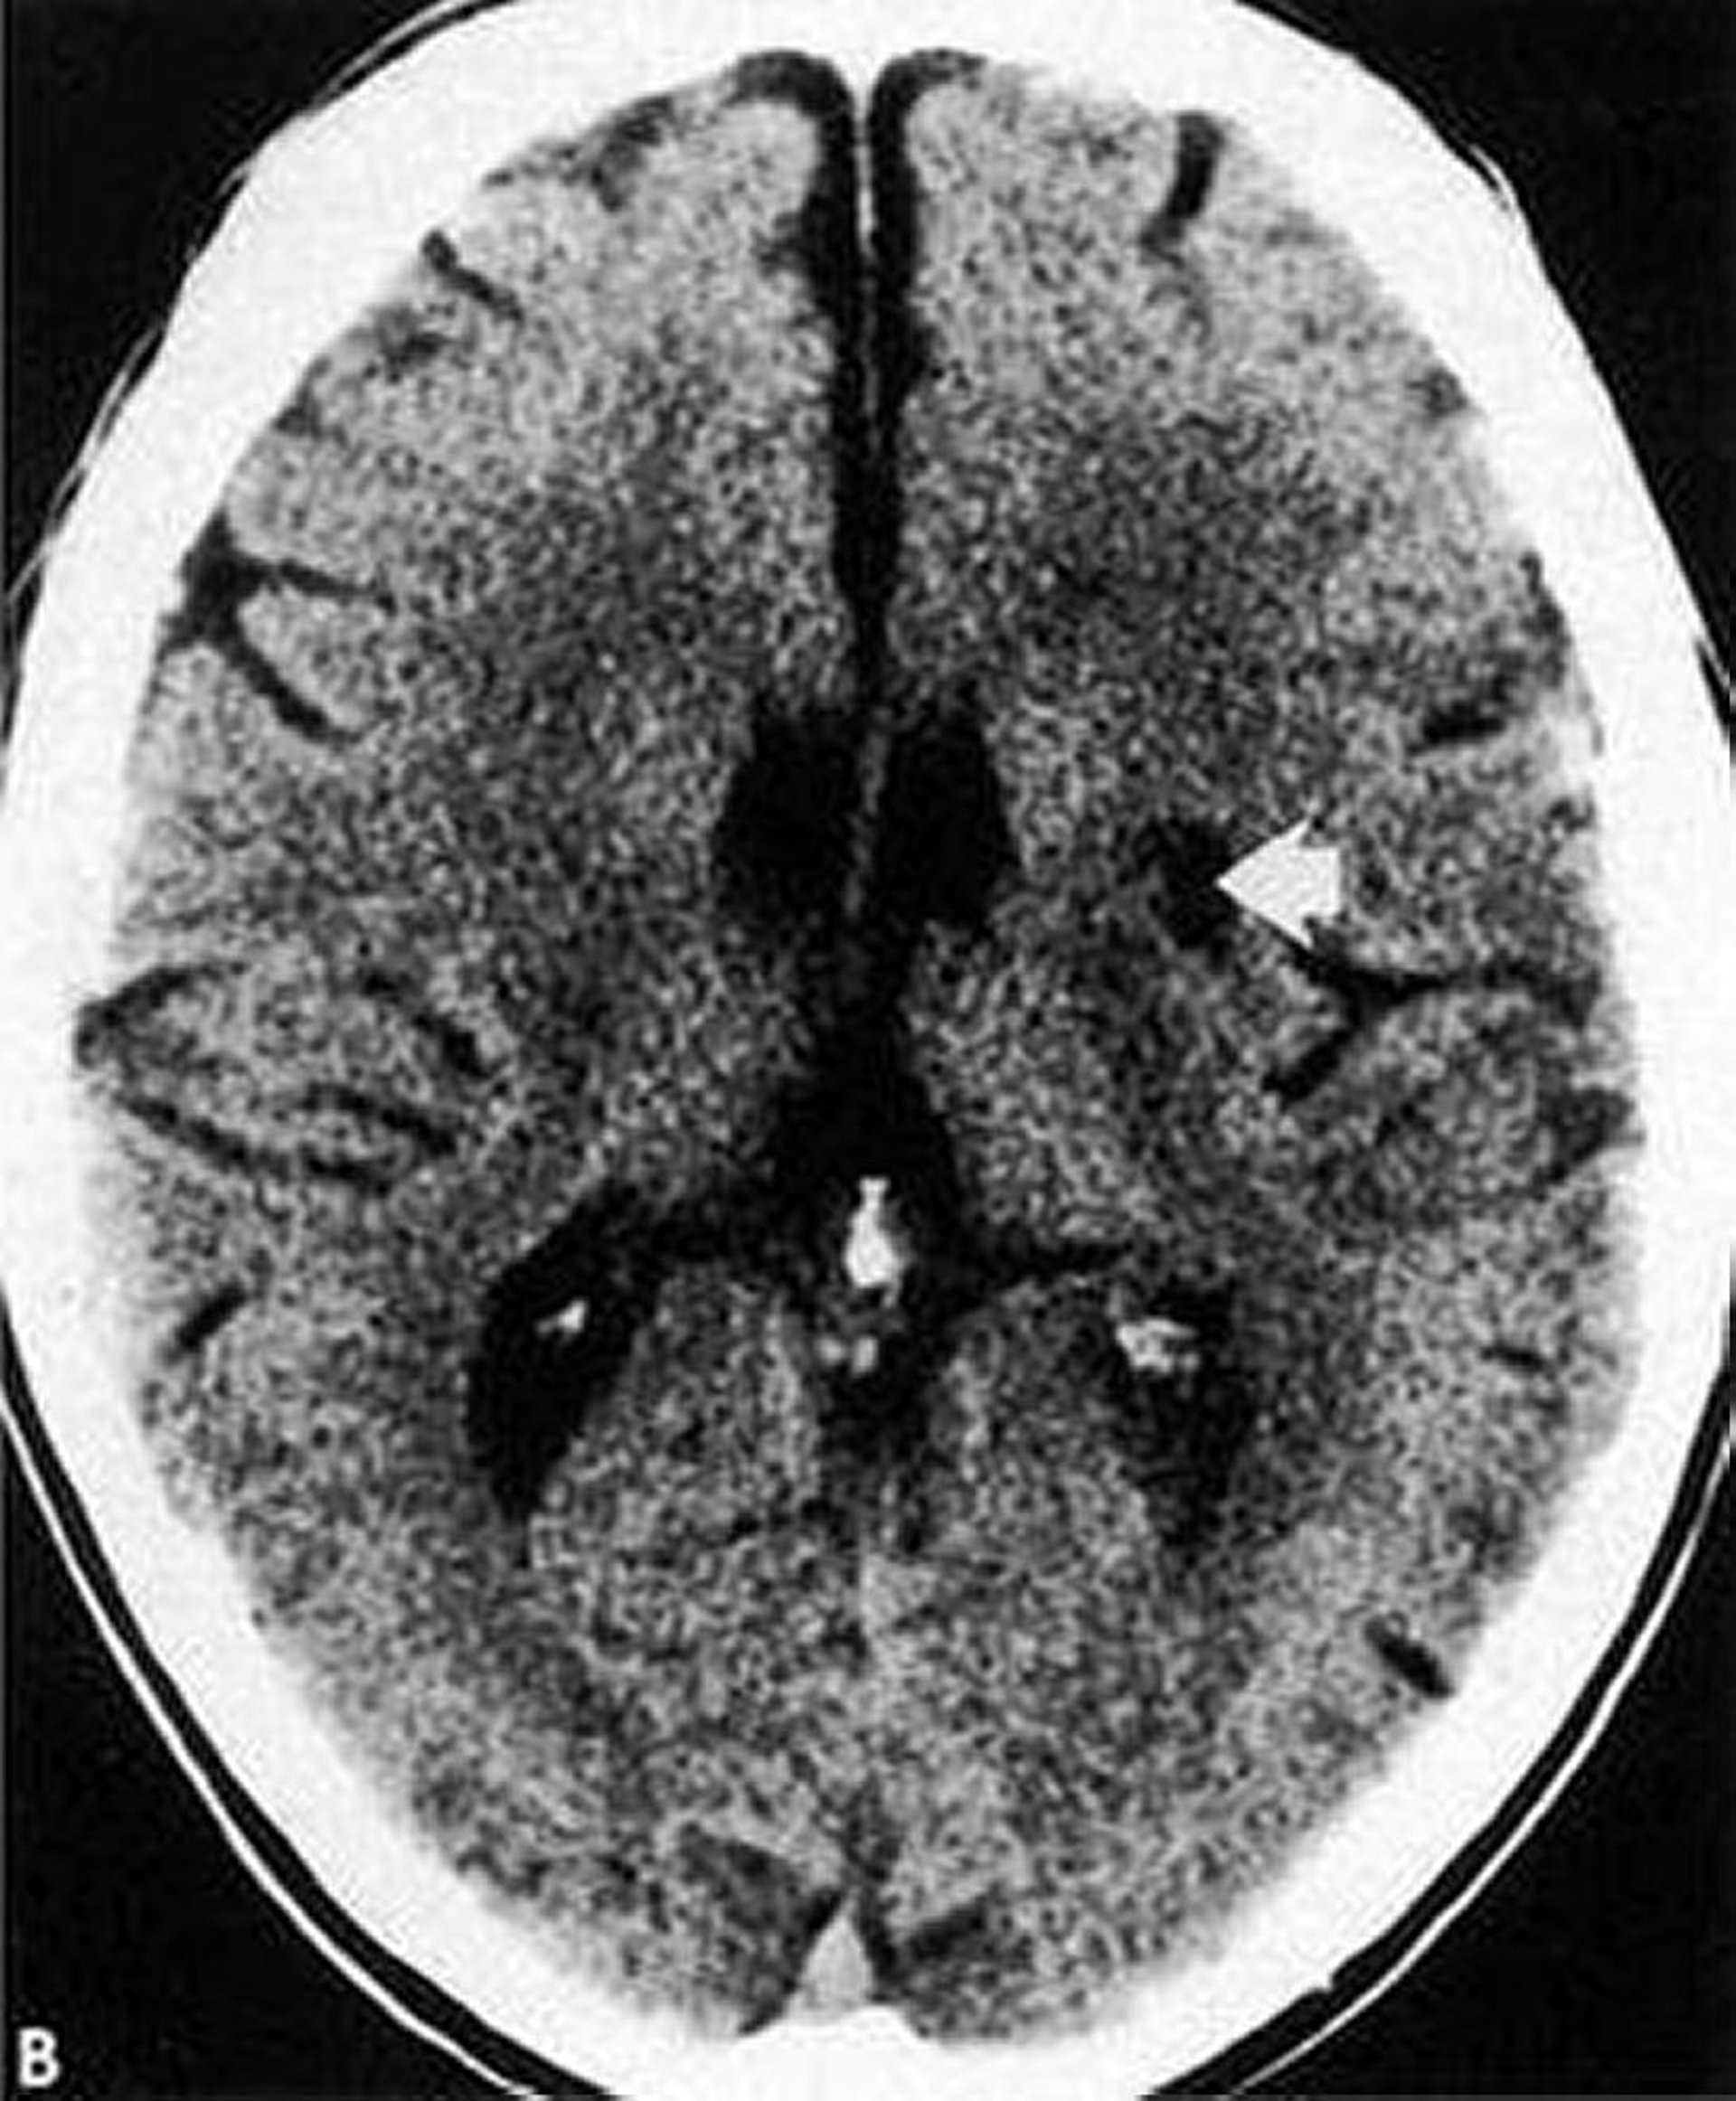

Lakunärer Infarkt

Diese CT-Aufnahme zeigt einen gut definierten lakunären Infarkt (Pfeil) mit geringer Dichte innerhalb der Basalganglien.

By permission of the publisher. From Geremia G, Greenlee W. In Atlas of Cerebrovascular Disease. Edited by PB Gorelick and MA Sloan. Philadelphia, Current Medicine, 1996.